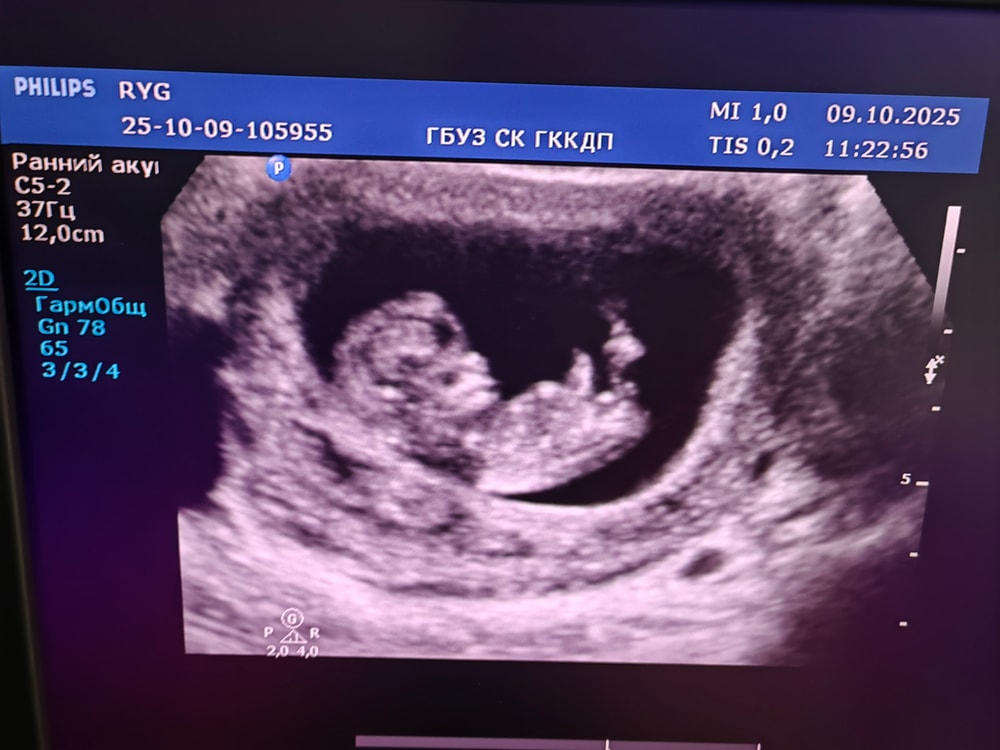

Сходила на узи

Результаты УЗИВсем привет, вчера писала пост о боли в пояснице, спасибо всем за поддержку, пошла сегодня на УЗИ, всё хорошо, малыш развивается правильно, есть тонус передней стенки, но сказали, что не страшно. Даже предположили пол малыша, скорей всего, мальчик, но это не точно, я всё время думала, что будет девочка. 😁 Еще сходила к терапевту, она дала направление на УЗИ почек.

КТР 39 мм

ЖМ 4,2 мм

ЧСС 170

Крошка❤️